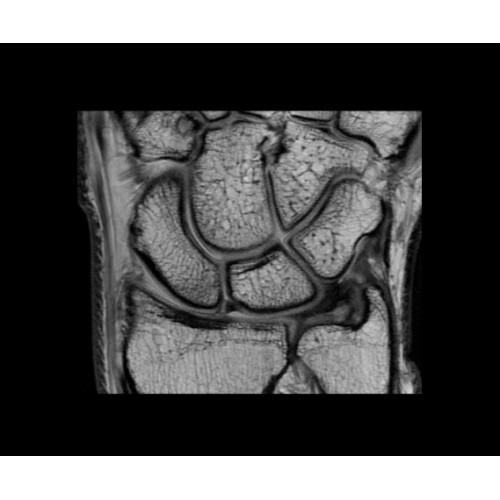

• NeuroWorks — универсальное решение для визуализации анатомии головного мозга, позвоночника, сосудов и периферических нервов с четкой дифференциацией тканей.